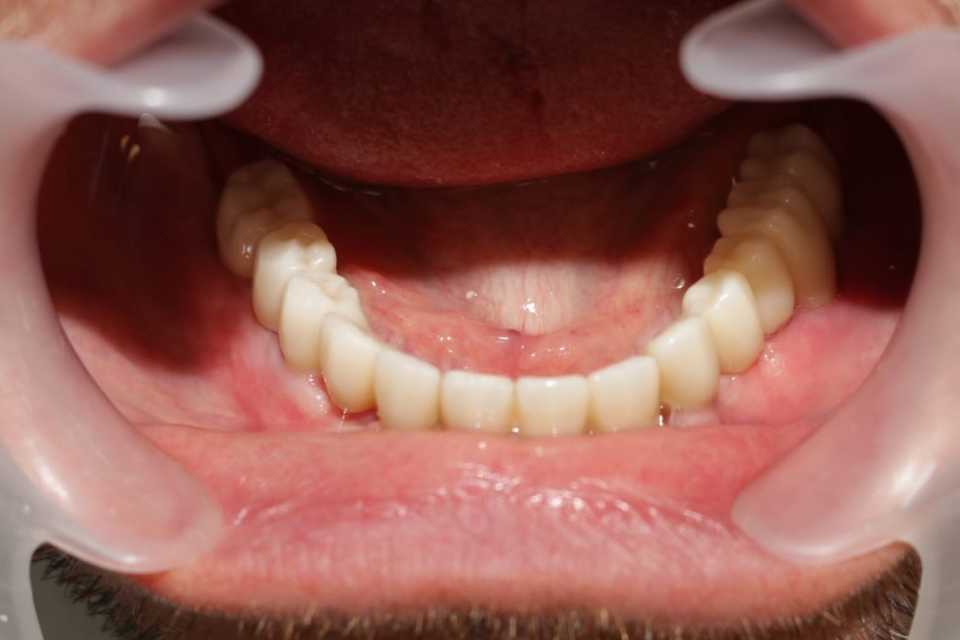

Pe parcursul unui an s-au efectuat adiții osoase la nivelul maxilarului (sinus lifting) și al mandibulei (tehnica Khoury, adiție laterală și verticală a zonei molarilor și premolarilor) cu ajutorul cărora am reușit inserarea a 6 implanturi Straumann la nivel maxilar și 8 implanturi dentare mandibular (4 Straumann, 4 MegaGen Anyridge).

Reabilitarea orala funcțională și estetică, s-a realizat cu ajutorul unei lucrări fixe cimentate la nivelul maxilarului din ceramica pe zirconiu și a 3 lucrări din ceramica pe zirconiu fixe cimentate la nivelul mandibulei.